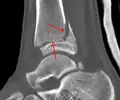

A triplane fracture of the ankle as seen on CT

- Triplane fractures are a special type of fracture that involves the immature skeleton. It has a coronal plane in the metaphysis, an axial plane in the physis, and a sagittal plane in the epiphysis.[14]